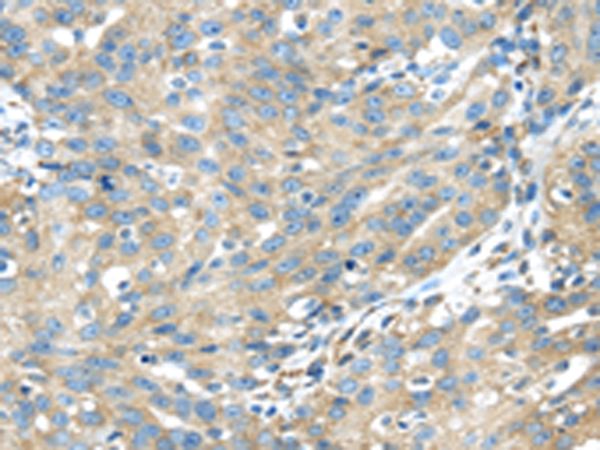

分类: 科研抗体货号: P08928别名: JTK1; IMD35应用: IHC反应种属: Human, Mouse